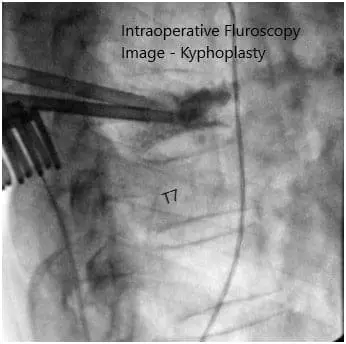

Intraoperative fluoroscopy images.

We employed fluoroscopy once again to check our level of operation and extended our incision slightly in the cephalad direction. At this point, we confirmed the level of the T6 vertebral body and started our open kyphoplasty.

First we inserted the Jamshidi needles under fluoroscopy through the pedicles to the vertebral body. We then inserted the cannulas for the kyphoplasty system bilaterally and obtained transpedicular biopsies, which were sent for histopathology.

At this point, we inserted the balloon on the patient’s right side and inflated it with contrast up to approximately 380 mmHg and this was checked constantly under both AP and lateral fluoroscopy simultaneously. We inflated the balloon to approximately 2 mL maintaining the pressure and to ensure that we remained within the confines of the vertebral body with the balloon inflation.

We did this then on the left side as well. The balloons were then deflated and removed and cement was introduced in a semi-liquid state, first on the right side, and then on the left side. Approximately 4 mL of cement was introduced from the right side and approximately 1.5 mL of cement was introduced from the left side.